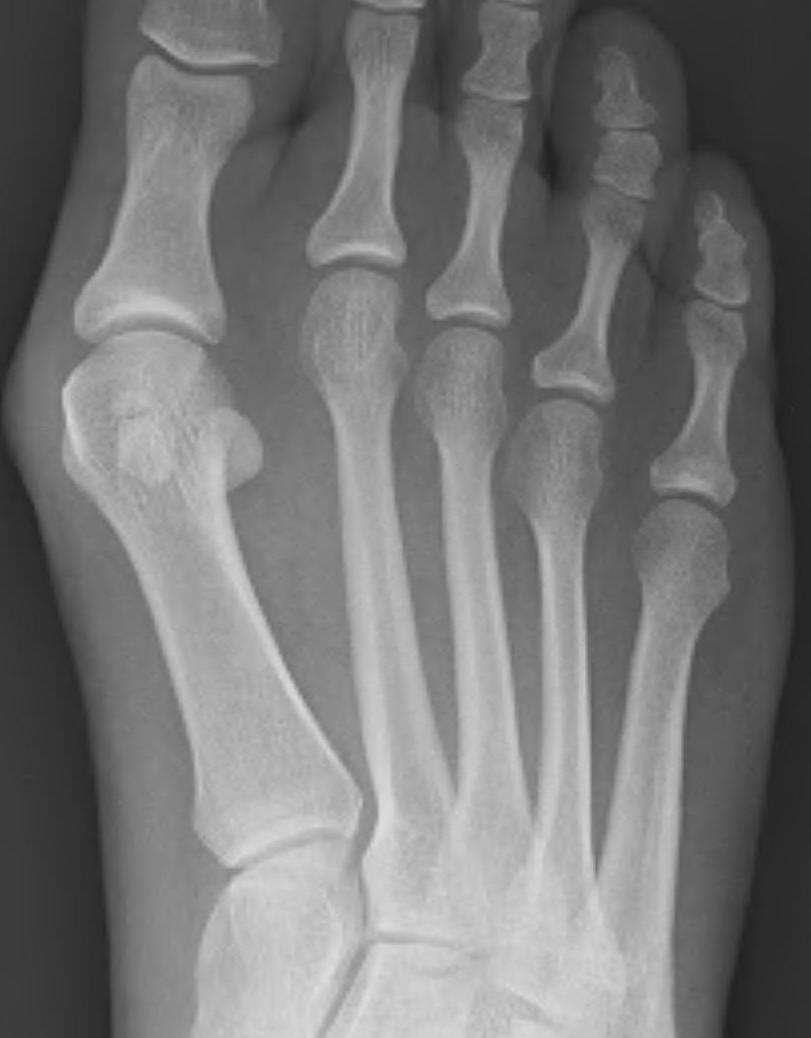

3. Altered forefoot biomechanics / Transfer metatarsalgia

| Hyper-extended MTPJ | Short 1st MT | 1st ray insufficiency syndrome | Iatrogenic |

|---|---|---|---|

| Claw toe / hammer toe | > 2 cm back from 2nd MT |

Splayed forefoot |

Bunion surgery |

| Cavus foot | 1st ray unloaded | 1st ray unloaded | MT head excision |

Cavus foot